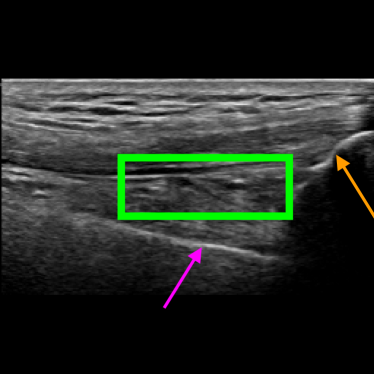

A joint recess can be distended due to three main reasons: it is filled with synovial liquid, it is filled with blood (a condition known as hemarthrosis), and its membrane is thicker due to an inflammation known as synovitis. When the SQR is distended, it appears thicker on the US image. In some cases this can be clearly visible because the joint recess appears as a large dark area. Figure 2 shows three examples of the longitudinal SQR scan. In Figure 2a the SQR is the dark area shown in the green box. In this case the SQR is thin, hence it is not distended. Vice versa, in Figure 2b the SQR is much thicker, indicating that it is distended. While Figure 2a and 2b show two characteristic examples with stark differences, there are borderline cases where the SQR appears slightly enlarged but it is not distended (see Figure 2c) or it is very slightly distended.

Refer to caption

(a) Non-distended SQR

(b) Distended SQR

(c) Borderline Non-distended SQR

Figure 2: Examples of longitudinal SQR scans

Figure 8 shows two US images that have been correctly classified by both approaches and that are relatively easy to classify by medical experts. Figure 8a shows an US image where the femur, the patella and the SQR are clearly visible, and the SQR is thin (i.e., not distended). On the other hand, Figure 8b shows an example of a Distended SQR. In this case, the SQR is clearly thick and hence distended.

Figure 8: Examples of images correctly classified by both solutions. The purple arrow points to the femur, the orange arrow points to the patella, and the green box indicates the SQR.